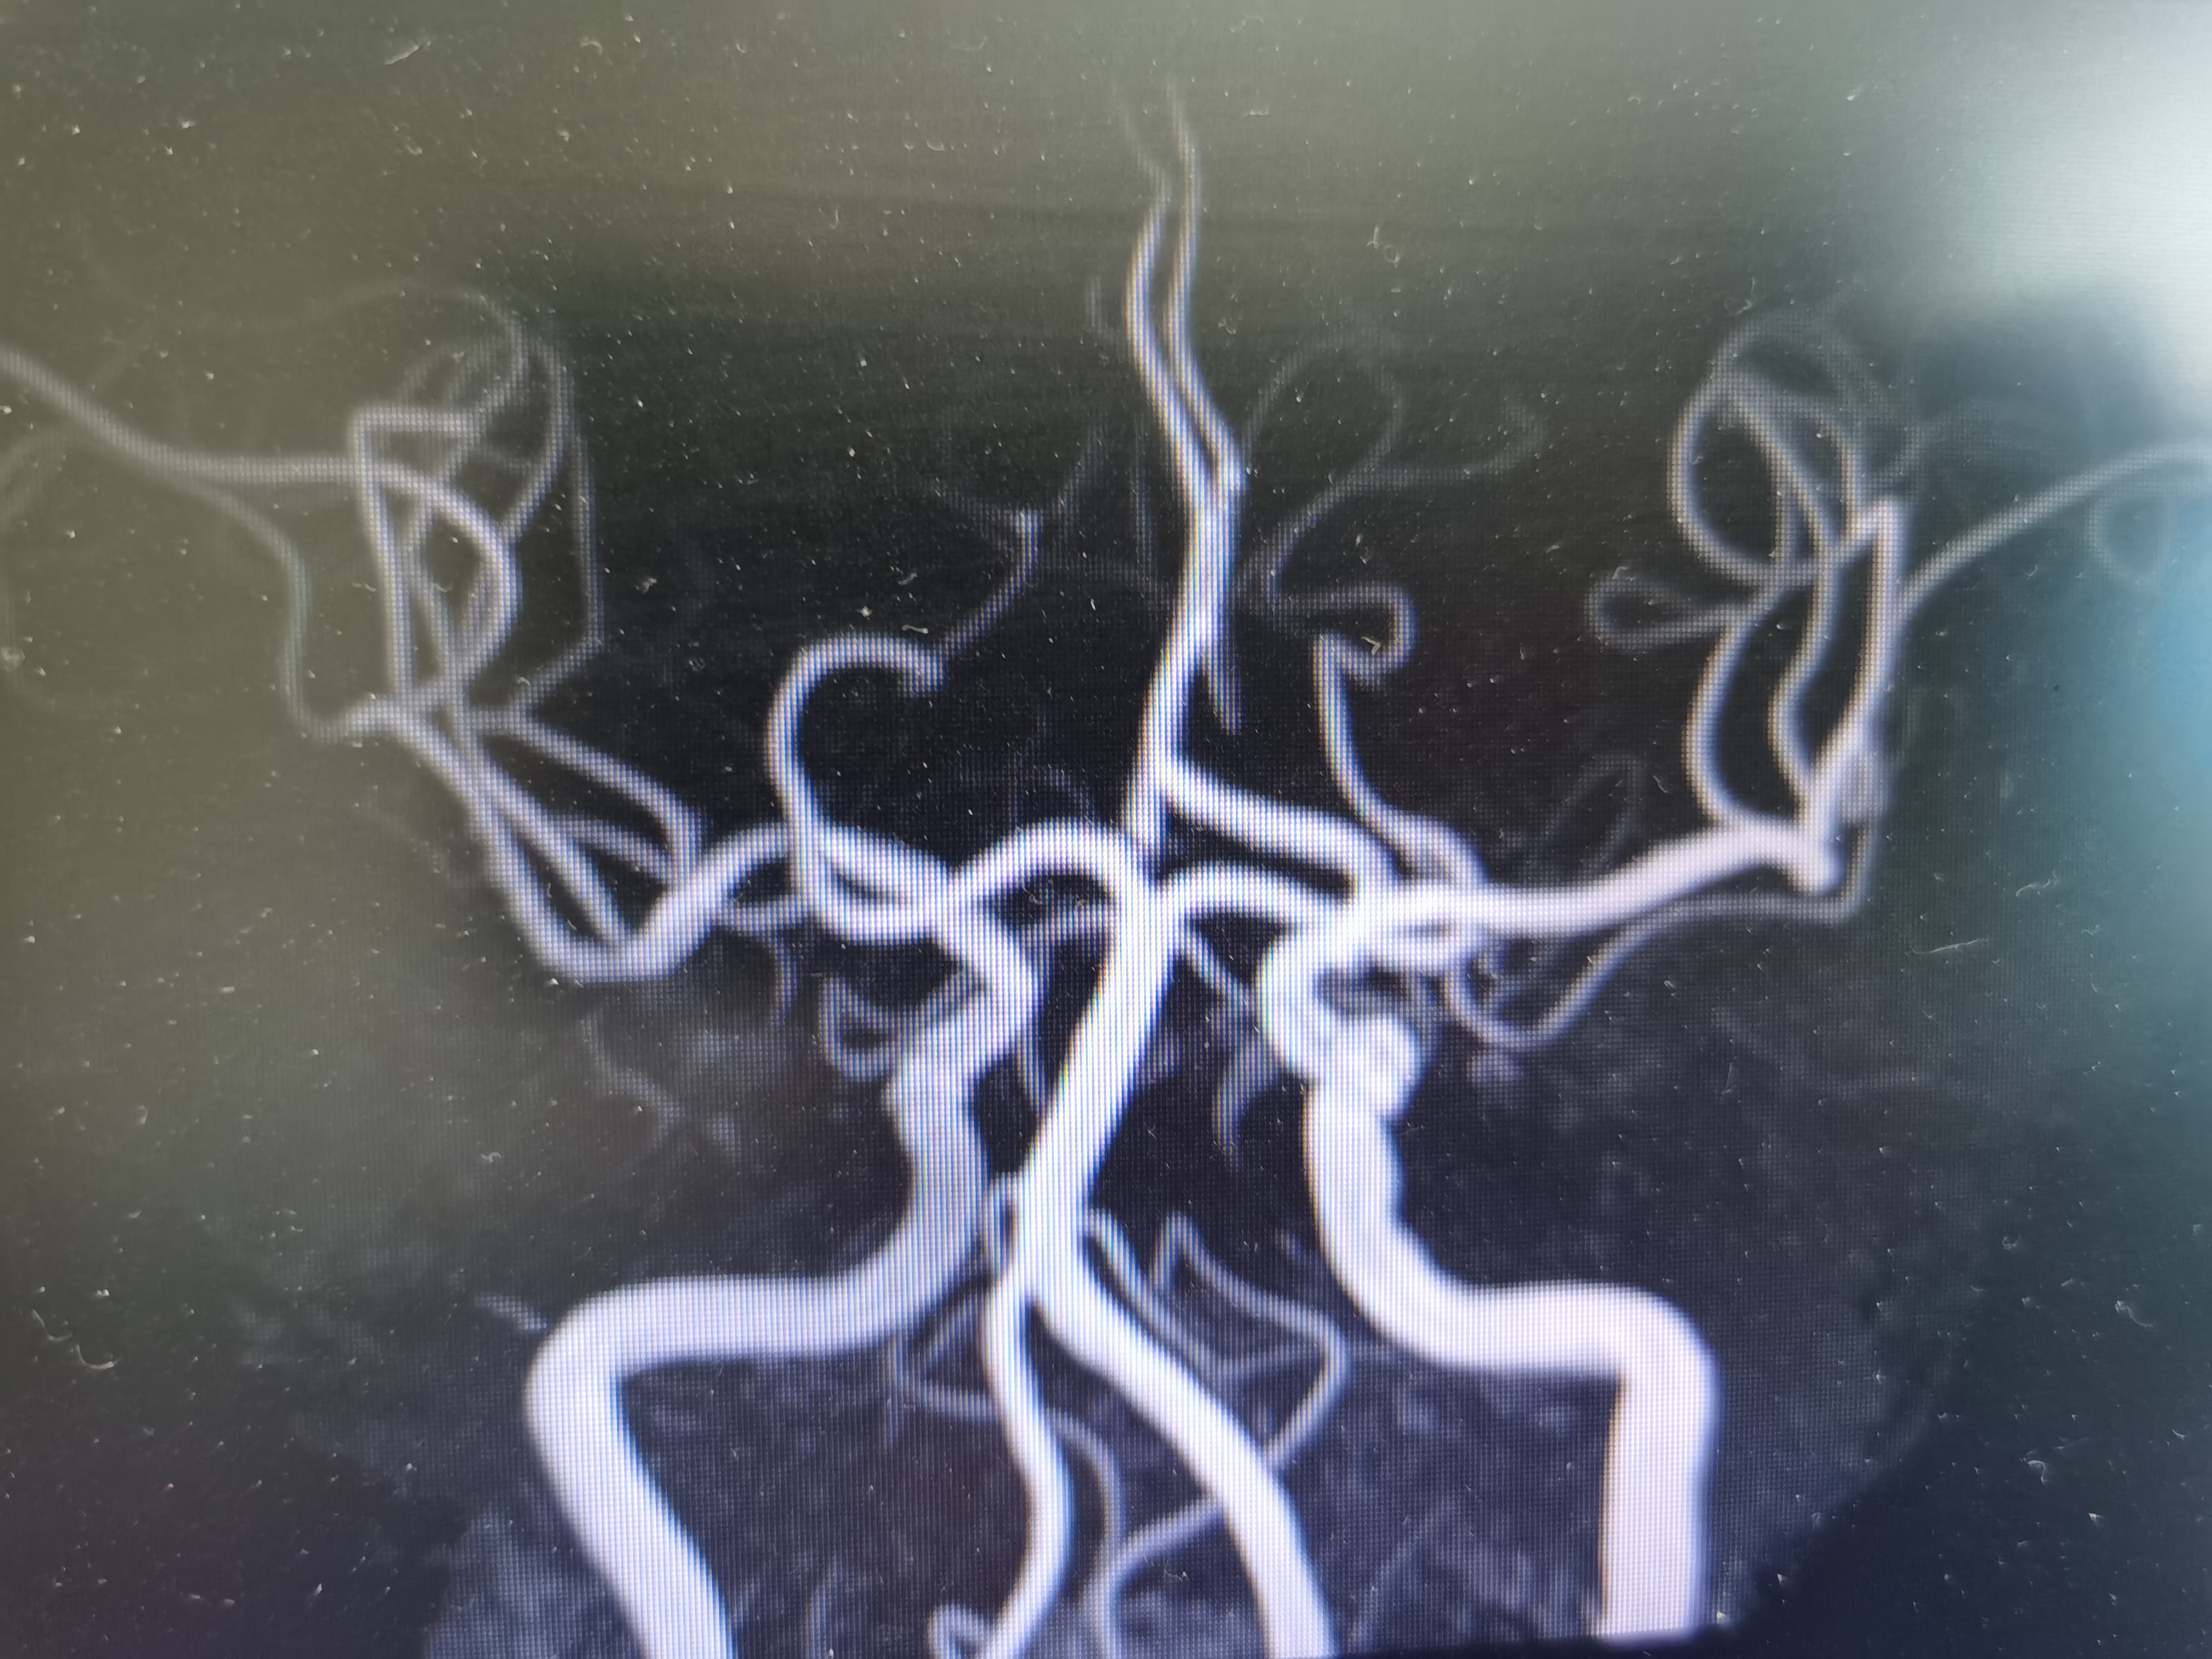

MRA示颅内段血管正常。

双侧大脑前动脉共干。